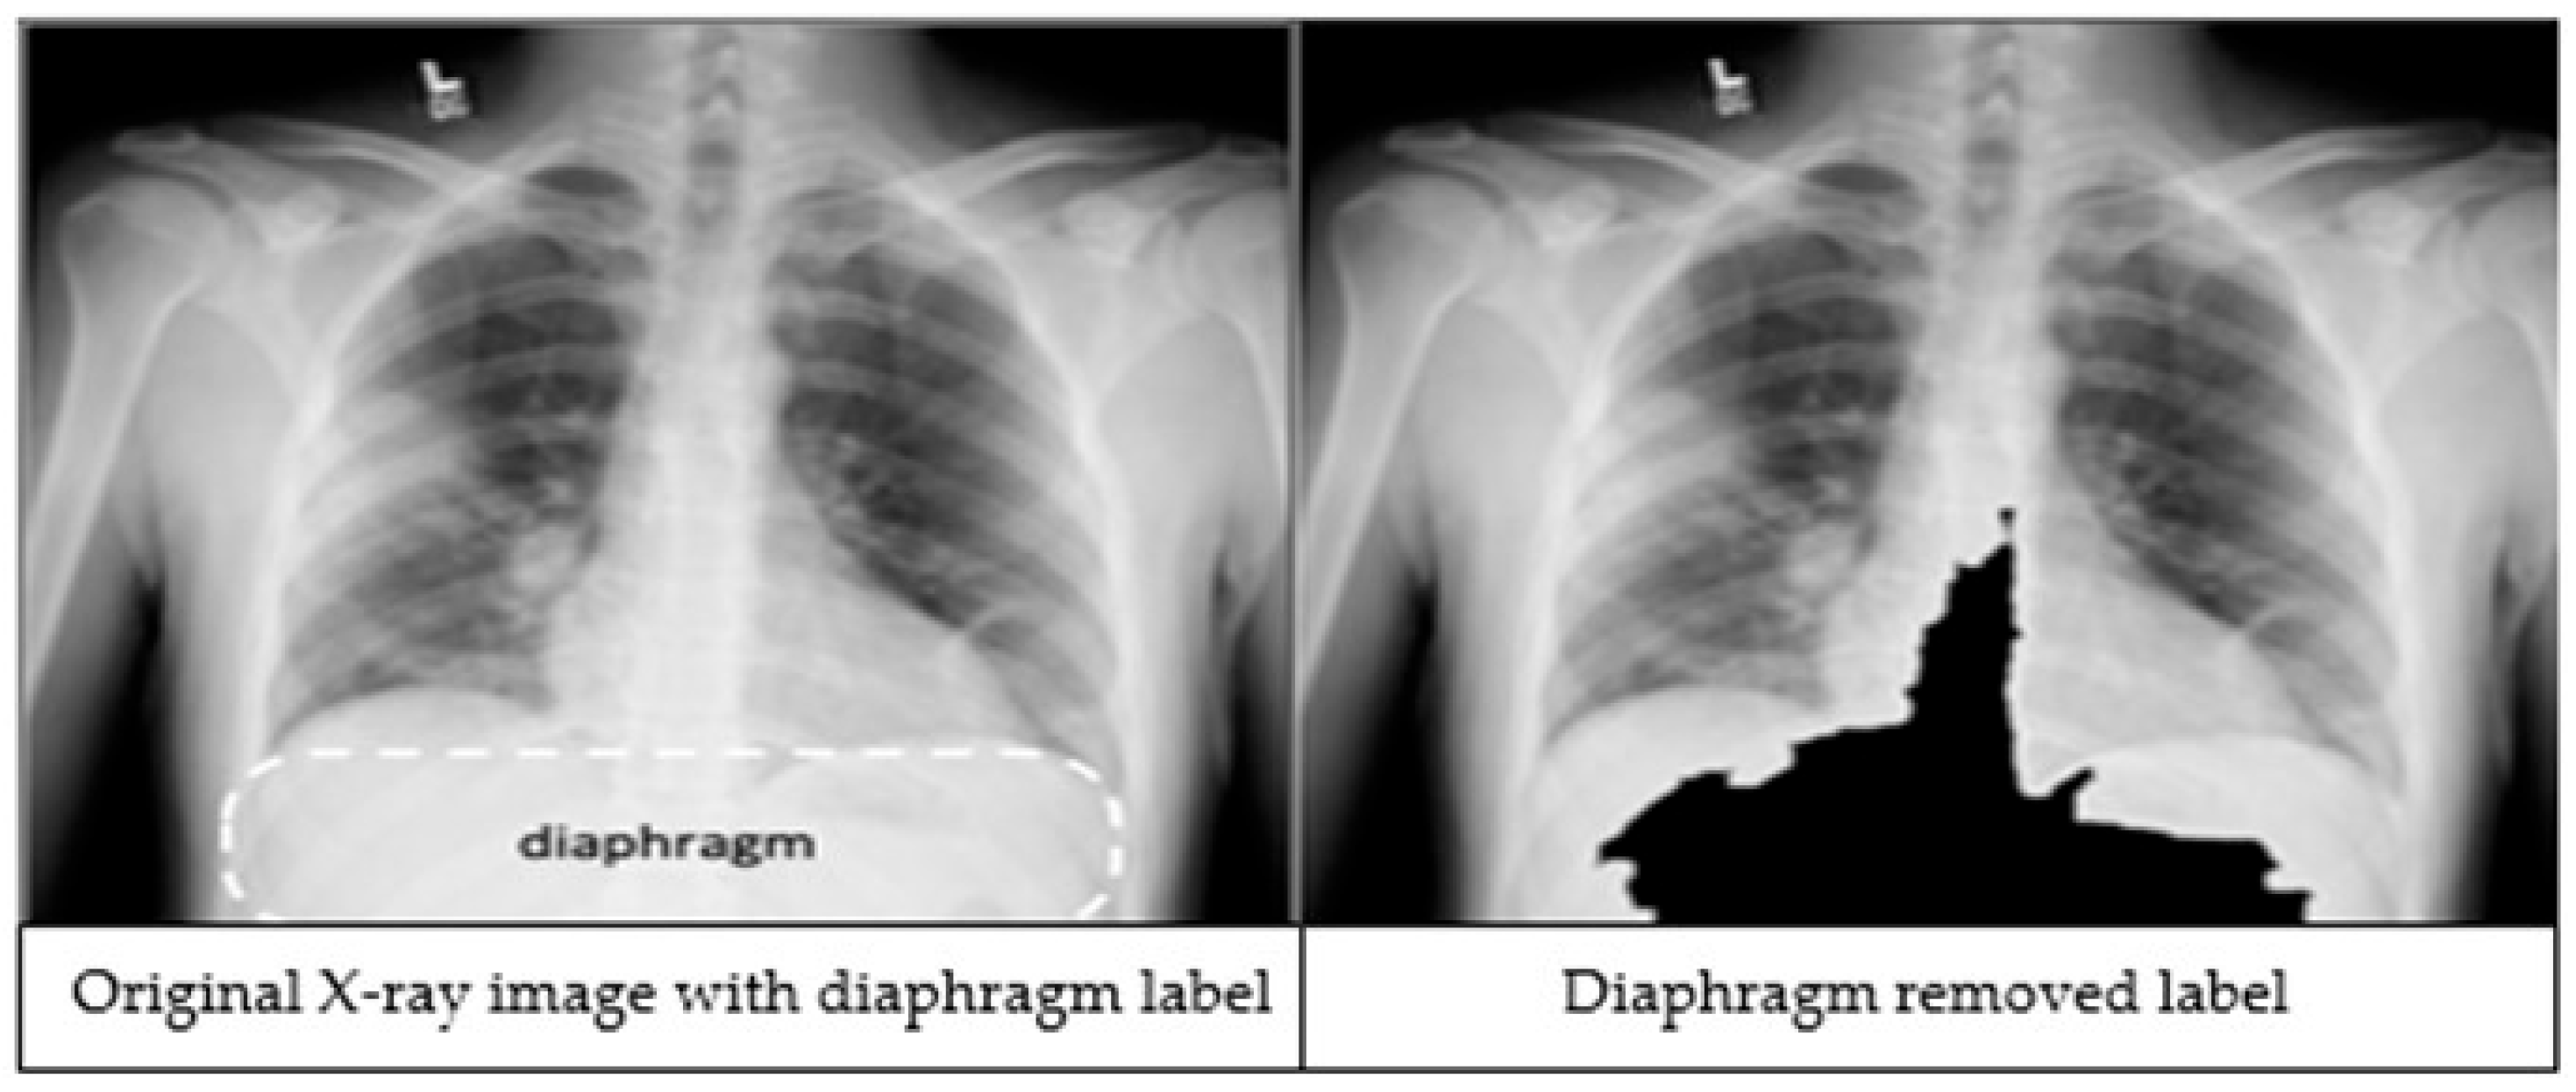

The third preprocessing technique focuses on improving classification accuracy by removing the diaphragm region (see Figure 2) from the X-ray images. The process begins by identifying the maximum and minimum pixel intensities, namely imax and imin respectively. A binary threshold t = imin + 0.9 * (imax − imin) is then applied to convert the image into a binary segmented image. Afterwards, a morphological closing is applied on the binary segmented image to make it a refined mask. Finally, a bitwise operation is performed using the mask image to remove the diaphragm area from the original image, resulting in an image which is called Id.

Figure 2.

An X-ray image showing the diaphragm region of the image within the dashed lines (left). The image after applying the diaphragm removal technique (right).

We applied image preprocessing techniques to automatically detect and remove the diaphragm region from chest X-ray images. Comparative analysis revealed that excluding the diaphragm significantly improved classification accuracy, increasing from 92.69% to 97.29%. While deep learning models are typically capable of learning relevant features without explicit segmentation, our findings demonstrate that removing irrelevant regions through preprocessing can enhance both the performance and robustness of the models.